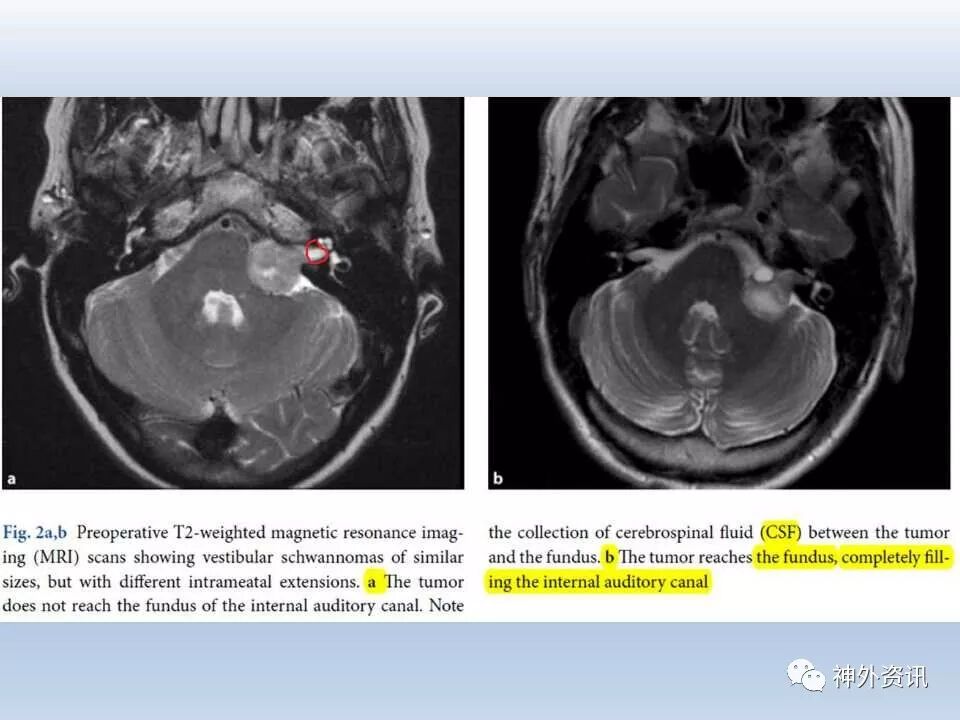

乙状窦后入路经典文献